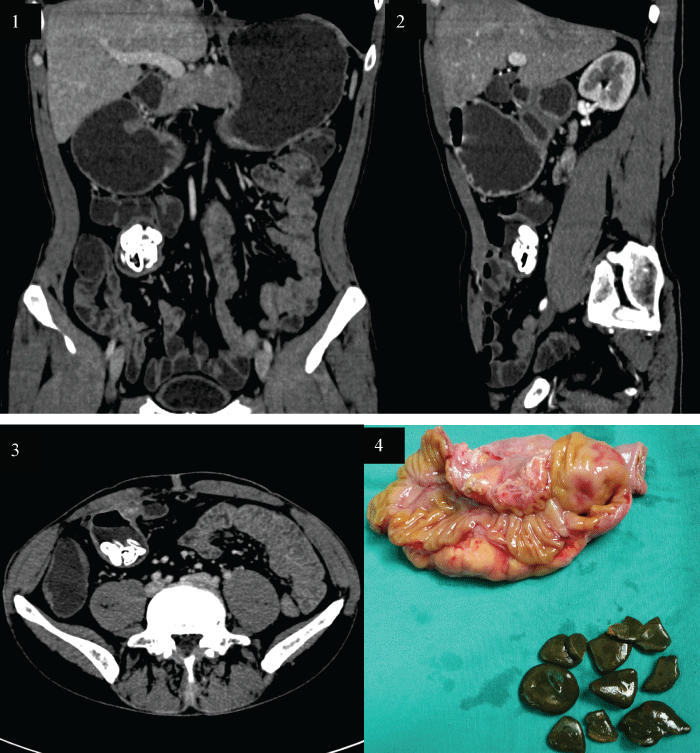

A 60-year-man was admitted to our hospital with the complaints of intermittent hematemasis for 6 months. The patients underwent side-to-side enteroanastomosis because of intestinal tuberculosis 30 years prior. Except for the iron deficiency anemia and decreases of the hemoglobin values down to 78 g/L, all the other laboratory values were within the normal range. Further investigation of the anemia included repeated colonoscopies and gastroscopies which didn't disclose a possible source of bleeding. Abdominal CT scan demonstrated multiple oval stones within regional blind end of small intestine and retained fluid was also noted in the sacculation (Figure 1, Figure 2 and Figure 3). Operation revealed an inflammed, oedematous, mesenteric sacculation in the blind end of intestinal afferent limb, which was located approximately 90 cm from the ileocecal valve. The involved segmental resection was completed with end-to-end stapled anastomosis. Surgery confirmed to be blind pouch syndrome and cut surface of the resected specimen showed mucosal ulcer and multiple stones in the lumen (Figure 4). The patient recovered well without any complications on the follow-up of one year.

Figure 1: